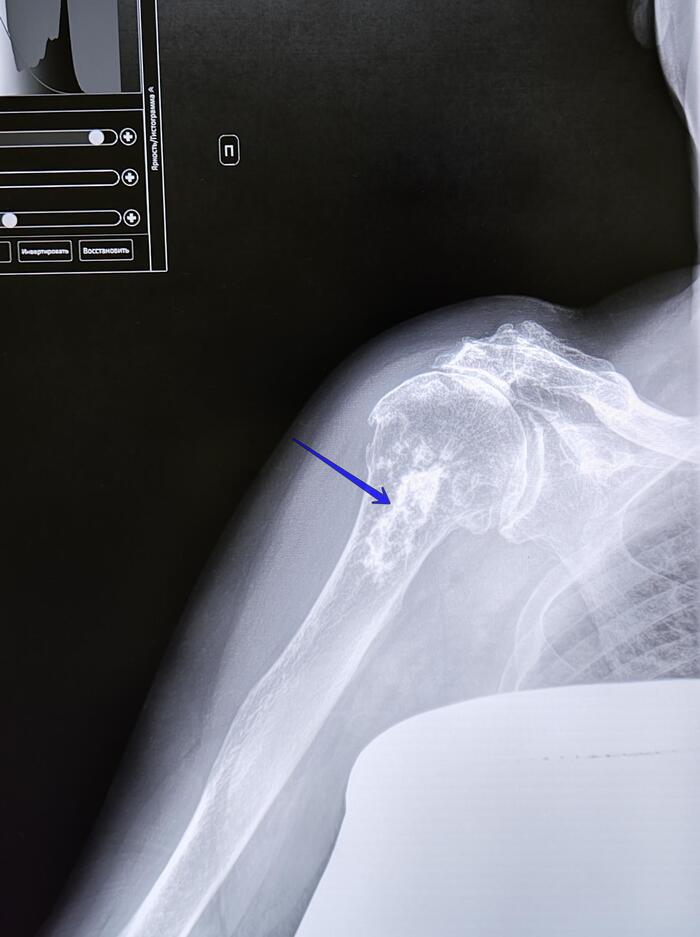

Эностоз-компактный островок остеосклероза

Эностоз, или костный островок, представляет собой доброкачественное образование в костной ткани, которое обычно обнаруживается случайно при рентгенологическом исследовании.

Основные рентгенологические признаки эностоза включают:

Очаговое затемнение:

На рентгенограмме эностоз выглядит как четко очерченный очаг повышенной плотности (гиперденсивный) в костной ткани.

Форма и контуры:

Образование обычно имеет округлую или овальную форму.

Контуры четкие, ровные, иногда могут быть слегка лучистыми или неровными, но без признаков агрессивного роста.

Связь с костными трабекулами:

Эностоз часто сливается с окружающими костными трабекулами, что создает характерный "лучистый" вид.